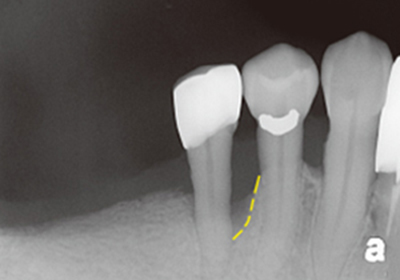

案例1

補骨前

補骨後